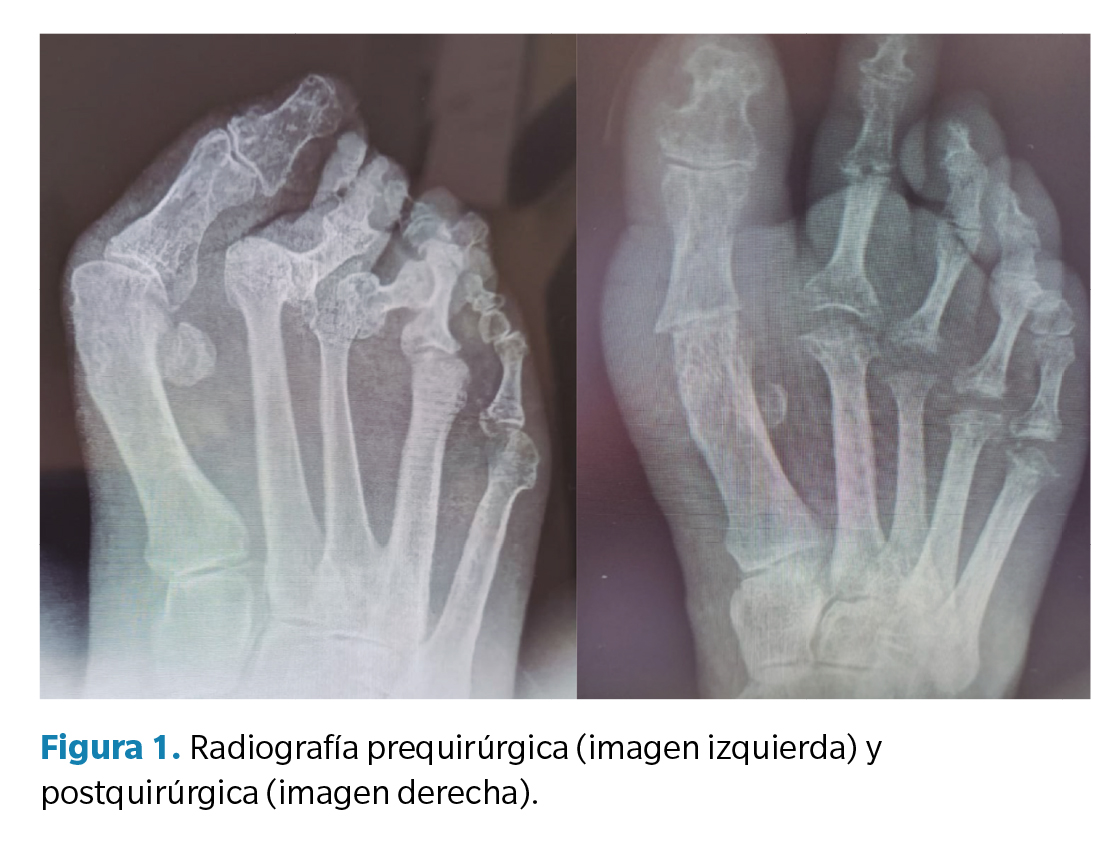

Previo a la recogida de datos, se llevó a cabo una anamnesis donde se recogieron variables genéricas (altura, peso, índice de masa corporal y lateralidad), categorización del riesgo quirúrgico (escala ASA), categorización del riesgo de trombosis venosa profunda (escala Autar), escala SF-36, escala AOFAS, motivo de consulta y valoración clínica del dolor (escala EVA). La valoración preoperatoria consistió en una exploración clínica, donde se observó la deformidad, tanto en carga como en descarga, y se llevaron a cabo diversas maniobras para valorar los rangos articulares de movimiento, prestando atención a la localización de dolor y/o de distintas hiperqueratosis asociadas a la deformidad. Asimismo, se llevó a cabo un estudio vascular en el que se palparon los pulsos pedio y tibial posterior acompañado de un eco-doppler y el índice de pie y tobillo (índice T/B). Además, se realizó un estudio biomecánico de la marcha, tanto baropodométrico como dinámico y, finalmente, se llevó a cabo un estudio radiológico (Figura 1) del pie a intervenir.

Junto con estas escalas, también se realizó un análisis radiológico de la deformidad en la Rx dorsoplantar en carga, donde se valoraron los siguientes ángulos: ángulo intermetatarsal, ángulo de hallux abductus valgus, ángulo de Merchan y ángulo interfalángico del hallux. Esta medición se realizó en la Rx preoperatoria y en la Rx postoperatoria al año de la intervención.

En cuanto a los ángulos radiológicos prequirúrgicos, se observa una media preoperatoria de 18.3º respecto al ángulo intermetatarsal I-II (IMA I-II) y de 48.4º respecto al ángulo hallux abductus valgus (αHAV). Tras la intervención, la media del IMA I-II fue de 15º y del αHAV de 24.1º. Respecto al ángulo de Merchan, se observa una media de 141.7 pretratamiento y de 141.6 postratamiento. En el caso del ángulo interfalángico, se obtiene una puntuación media de 5º pretratamiento y de 3.3º postratamiento (Tabla 3).